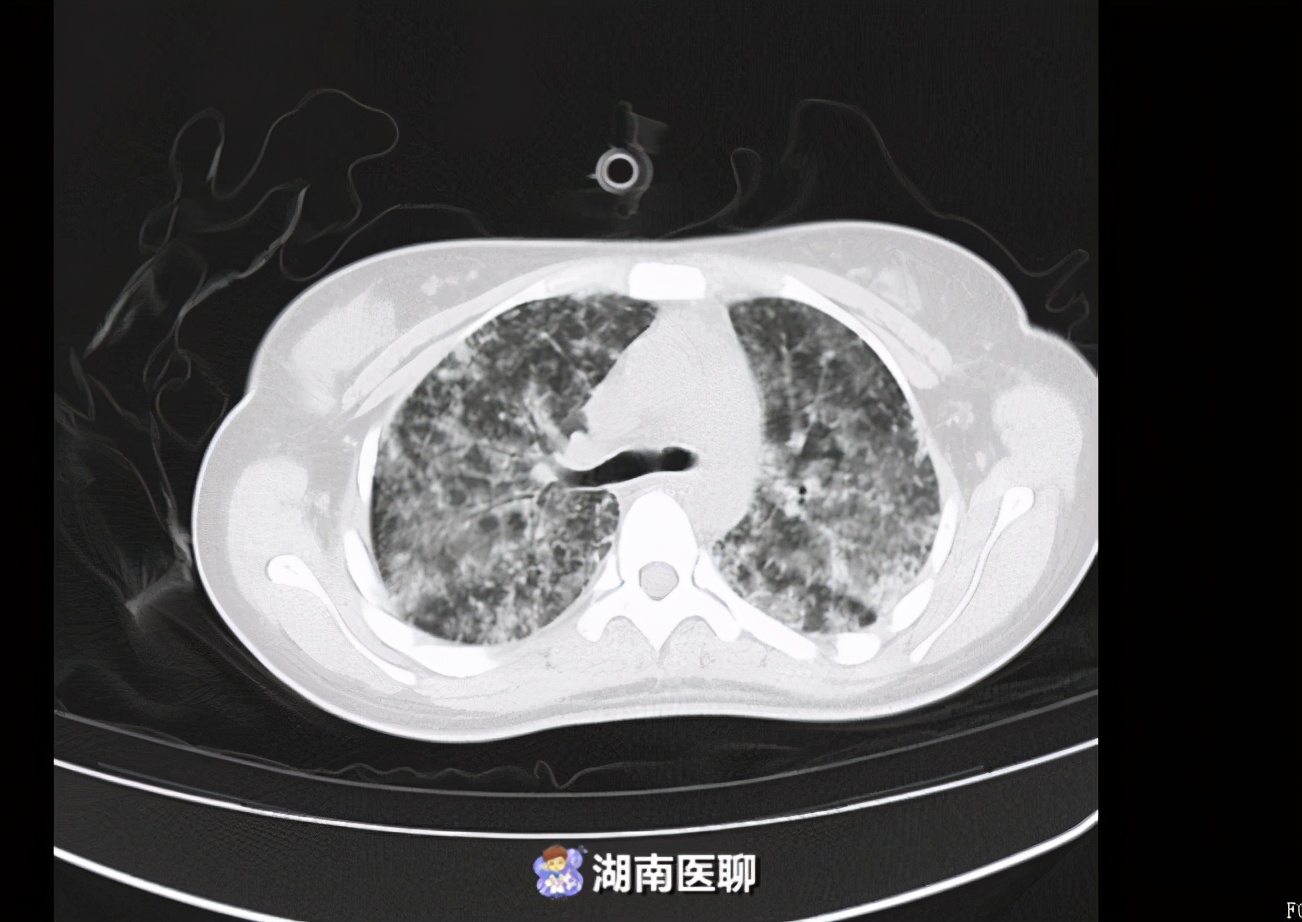

CT提示弥漫性肺泡出血。

医生从小英肺部灌洗出大量血性分泌物。